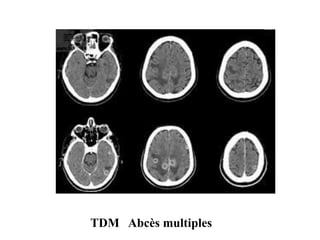

LES ABCES: A PYOGENES

TDM :réalisé en première intention(contexte d’ urgence

sans et avec injection de produit de contraste

• TDM Sans inj: lésion hypodense .

• Après inj: Lésion à centre hypodense avec

rehaussement périphérique en COCARDE en

couronne ou en COQUE .

• Œdème péri lésionnel hypodense

TDM Abcès multiples